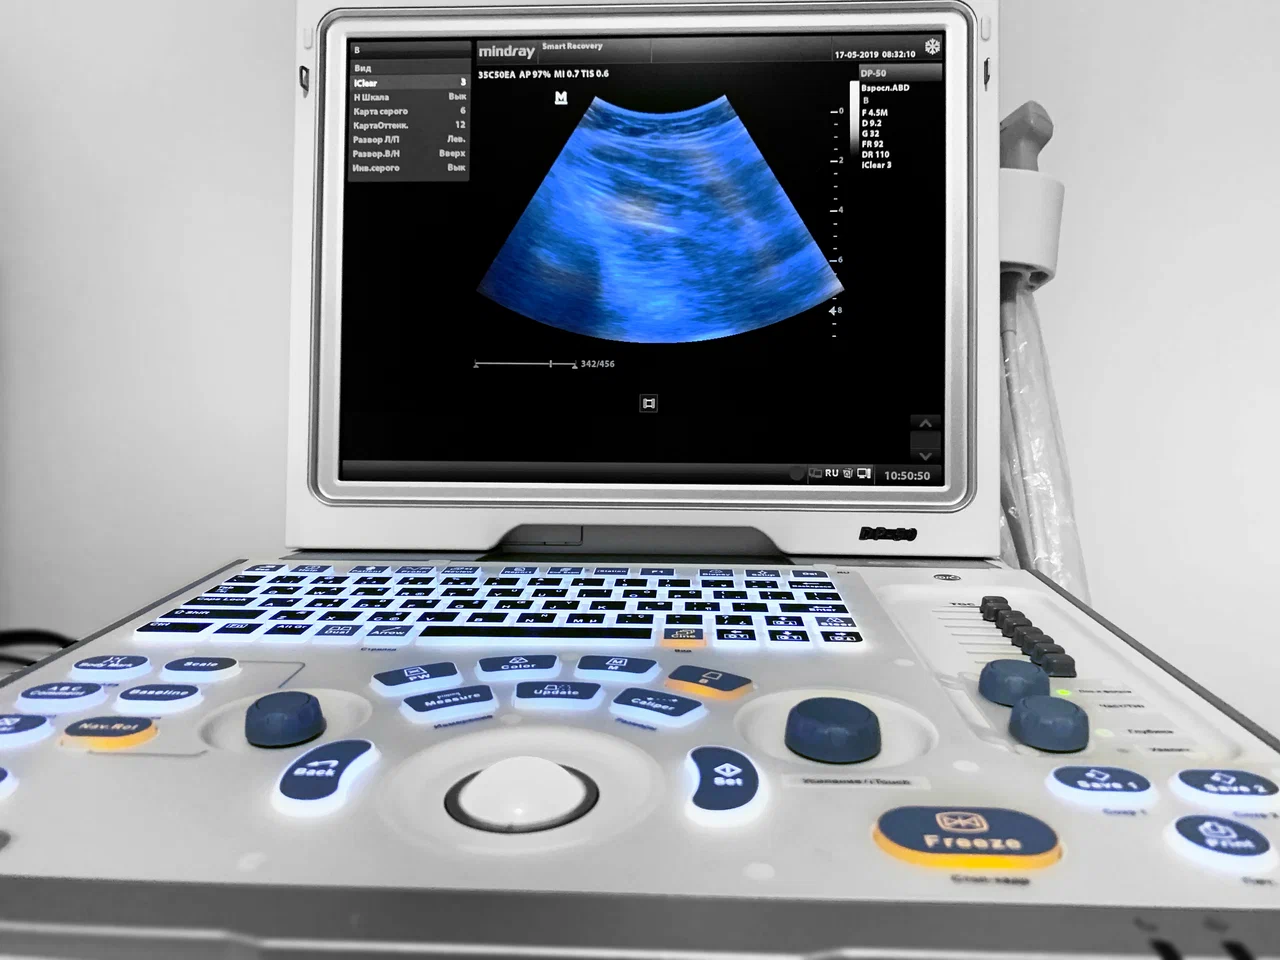

Ультразвуковое исследование

УЗИ-диагностика травм и контроль восстановления

Ультразвуковая диагностика (УЗИ) — это современный, безопасный и высокоинформативный метод исследования, который широко применяется для диагностики травм, заболеваний и контроля восстановления опорно-двигательного аппарата и внутренних органов. В спортивной медицине и медицине активного образа жизни УЗИ используется не только для постановки диагноза, но и для динамического наблюдения за состоянием тканей на фоне лечения и физических нагрузок.

Современные технологии УЗИ в Smart Recovery

Диагностика травм и функциональных изменений требует применения высокоточного оборудования. В клинике используется универсальный ультразвуковой сканер Samsung V7-RUS, разработанный компанией Samsung Medison Co., Ltd.

Процесс проведения ультразвуковой диагностики максимально комфортен для пациента. На кожу в области исследования наносится специальный гель, который улучшает контакт с датчиком. Датчик, подключённый к сканеру, посылает ультразвуковые волны и принимает отражённые сигналы, создавая изображение внутренних органов на экране. Вся процедура обычно занимает от 10 до 30 минут и не вызывает дискомфорта. Результаты исследования зачастую можно получить сразу после окончания сеанса.

Особенность ультразвукового исследования заключается в его безопасности, доступности и универсальности. В отличие от других методов визуализации, УЗИ не использует ионизирующее излучение, что делает его безопасным для всех возрастных категорий, включая беременных женщин и новорождённых. Высокое разрешение современных аппаратов позволяет увидеть мельчайшие детали и динамику изменений в реальном времени. Использование технологий цифровой обработки изображений и дополнительных режимов сканирования, таких как допплерография, делает УЗИ незаменимым инструментом для точной и быстрой диагностики широкого круга заболеваний.